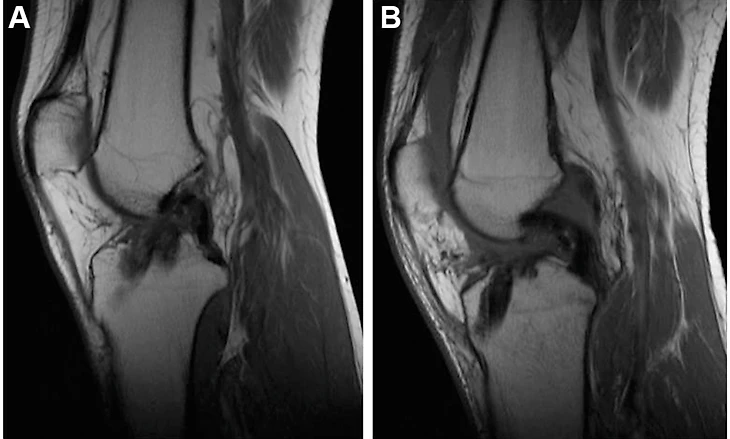

На практике Джало это никак не сказывалось, он числился основным и получал осторожные авансы в пользу блестящего будущего. А 4 марта 2023 года аплодисменты полностью затихли на фоне новости о разрыве крестообразной связке у футболиста - матч против Ланса, который закончился для Тьягу уже на 11 минуте, так и остался на текущий момент последним для игрока.

Характер травмы, способной определить вектор развития карьеры Джало вплоть до ее завершения.

Разрыв крестообразных связок в футболе считается одной из самых страшных травм. Ключевыс фактором опасности ее возникновения считается то, что получить ее можно в любой момент даже по случайности - в 70% случаев ничто заранее не предполагает подобного разрыва, обычный неудачный стык или неправильно выставленная опорная нога запросто может привести к подобной травме.

Добавляет драматизма и долгий срок реабилитации - коленные связки заживают минимум полгода, а последующие месяцы восстановления прежней работоспособности в усиленном темпе лишь усугубляют состояние мышечной ткани вокруг поврежденной связки, что зачастую провоцирует возникновение новых травм, в этот раз мышечных. Тем более разрыв связки сигнализирует о том, что суставы и связки игрока подвержены подобным травмам, то есть велика вероятность рецидива или разрыва другой связки после продолжительного восстановления. В 20% случаев, зафиксированных в профессиональном футболе за последние 15 лет, травма возвращалась вновь.

Крестообразные связки отвечают за всю работу колена, они стабилизируют коленный сустав и не позволяют голени смещаться в стороны. Помимо прочего, на их работе строится и распределение мышечного давления при ходьбе и беге - степень напряженности мышц напрямую зависит от состояния крестообразных связок. Учитывая динамику задействования связок при движении колена, для ее разрыва достаточно одного сильного контакта в определенном месте - вроде удара, что приведет к смещению голени в противоположную от давления сторону и порвет связку. Помимо прямого контакта, даже обычное смещение голени в момент приземления после прыжка или неудачного падения способствует развороту головки кости в другом направлении, что также приведет к разрыву скрепляющей связки.

Проблема реабилитации заключается также в том, что срастаясь, связка не гарантирует былой работоспособности, точнее прежней анатомической целостности. Колено может потерять маневренность, а процесс бега чаще всего сопровождается болевыми ощущениями на протяжении многих месяцев, а иногда и лет. Меняется манера движения тела, что влияет на мышцы, спортсмен учится заново работать с собственным телом. И здесь на дальнейшую карьеру влияет подход игрока к процессу восстановления и последующей карьере в целом. Ярчайший пример - Алессандро Дель Пьеро, переживший в 24 года разрыв сразу обеих связок колена, потерявший после реабилитации прежнюю скорость и технику, компенсировав их отсутствие тактическим интеллектом. Алессандро в своей биографии писал о том, как после возвращения он начал учиться работать на поле головой, управляя собственными инстинктами, подчиняя их воле и разуму. Если раньше все делалось на рефлексах и скорости, отныне каждое движение подкреплялось сознательным выбором.

Чаще всего после разрыва следует операция. А хирургическое вмешательство означает удаление поврежденного участка связки, что сразу дестабилизирует движение колена в сравнении с его здоровым состоянием. Но без операции сложно обойтись, ведь место надрыва при заживлении сохраняет проблемное состояние, и повторный разрыв - это лишь вопрос времени при прежних нагрузках.